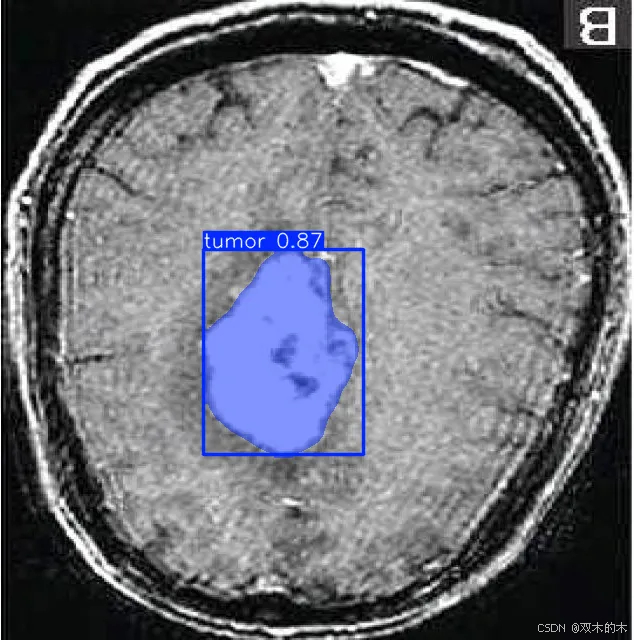

数据收集:收集表示要检测的类的图像。在此示例中,我们将使用 BRAIN-TUMOR 数据集,其中包含来自 roboflow 的 834 张图像。

链接 :https://universe.roboflow.com/iotseecs/brain-tumor-yzzav

YOLOv11 作为强大的实例分割工具脱颖而出,结合了尖端的准确性和效率。按照本文中概述的步骤,您可以在自定义数据集上有效地训练 YOLOv11 模型,并将其功能用于各种应用程序。